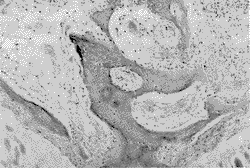

病因尚不清楚,多數學者認為與常染色體顯性遺傳有關,部分為常染色體隱性遺傳。是由遺傳性中胚層發育障礙造成的結締組織異常累及鞏膜、骨骼、韌帶等而出現相應症狀,由於結締組織廣泛分布於全身,所以患兒常有多組織、多器官的改變。